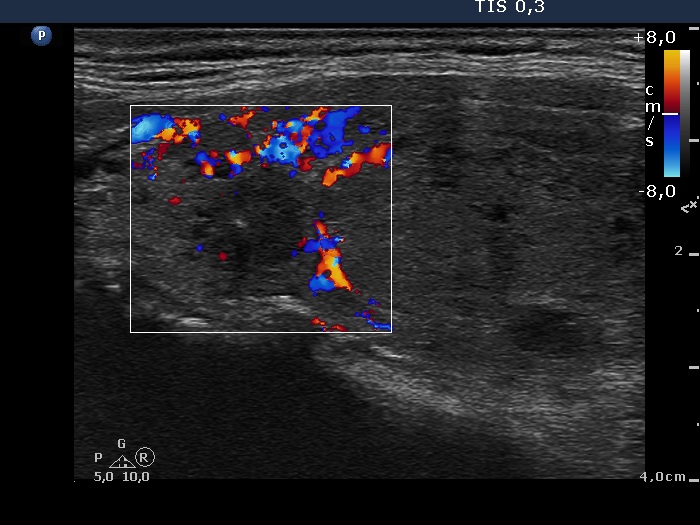

Case 441 (ultrasonographic picture 8)

Upper part of the left lobe, longitudinal view, color Doppler mode. The vascularization is increased in the extranodular part of the lobe while the hypoechogenic area is avascular.